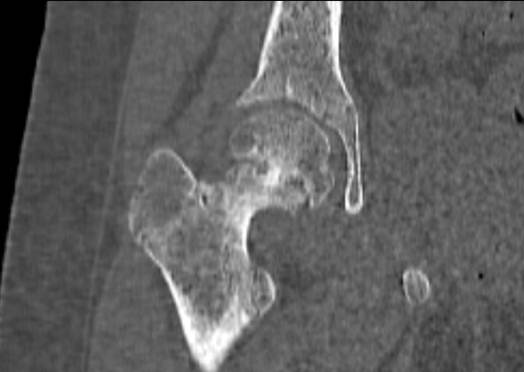

РК

– томография тазобедренных суставов девочки 10 лет с юношеским эпифизеолизом

головки бедра справа. Скан во фронтальной плоскости. Отчетливо видна костная

«сшивка» зоны роста.